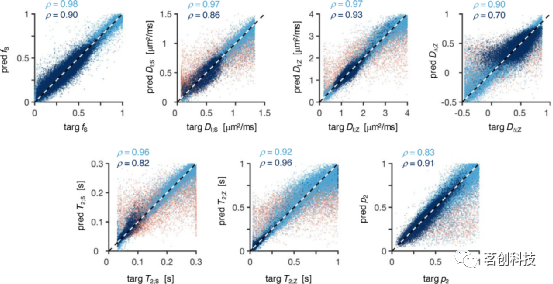

图2显示,基于SNN的估计与地面真值参数目标相关良好,大多数参数的线性相关系数接近或高于0.9。参考图着重于使用优化协议生成的silico S(τE,B)数据和均匀混合的随机类WM样本(fbrain=0.5)训练的网络性能,并区分了均匀随机采样获得的参数(浅蓝色点)和来自体内非皮质大脑数据的参数(深蓝色点)的性能。红点对应于从低分量特定信号分数导出的参数向量。当DΔ;Z值较小时,可以观察到性能较差,即无论地面真值如何,网络的输出DΔ;Z≈0.3。这可归因于在区分|DΔ;Z|<0.5分量的扩散加权信号时存在的固有困难。此外,当T2;Z时间比最大回波时间长时,目标与估计的对应关系较差。

图2.地面真值参数与神经网络预测的散点图。

图5A显示,使用旋转不变量训练SNN会导致目标参数和估计参数之间的相关性略强(与图2的散点图相比)。当DΔ;Z值较小时,精度有了相当大的提高,此时完整SMR模型(见图2)中观察到的常量DΔ;Z≈0.3行为不再存在。将旋转不变性(RotInv)网络应用于看不见的体内Sl={0,2}数据集会产生具有解剖学合理对比的参数图(见图5B)。可以看到,RotInv DΔ;Z图具有更平滑的外观,并且比其非旋转不变SMR对应图更好地界定了皮质/非皮质实质(将图1的第四列与图5B进行比较)。